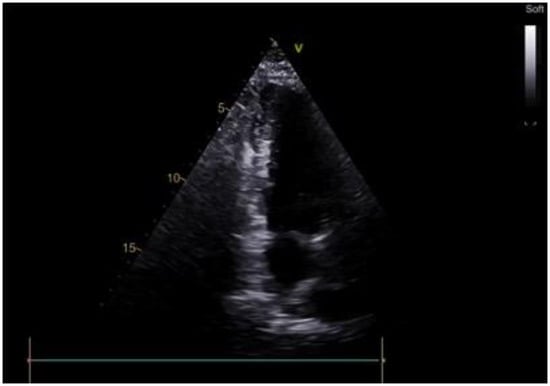

2.1. Case Scenario

2.2. Surgical Procedure